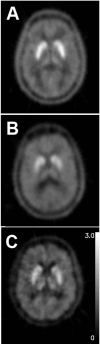

- Brooks DJ, Frey KA, Marek KL, et al. Assessment of neuroimaging techniques as biomarkers of the progression of Parkinson's disease. Exp Neurol. 2003;184(Suppl 1):S68–S79. - PubMed